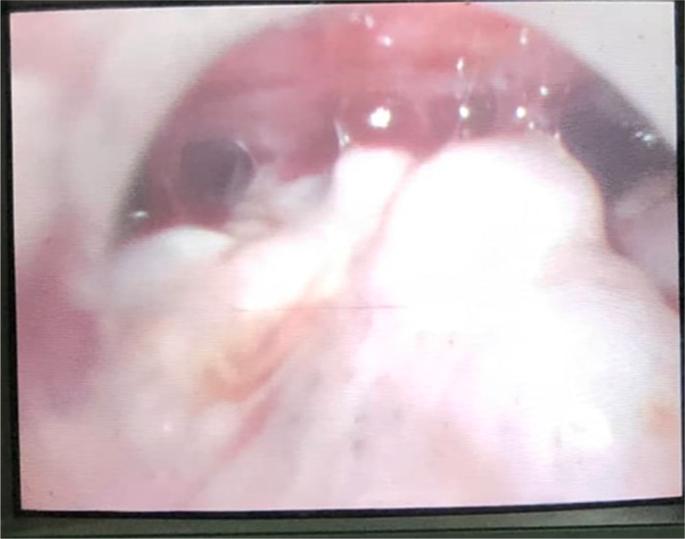

CASE PRESENTATION

we report an unusual presentation of advanced gastric adenocarcinoma in 39-year-old man, who presented to our hospital with inguinal hernia without obvious gastrointestinal symptoms. He had strong family history of cancer, heavy smoking habit and weight loss. The intra-operative procedure identified a cyanotic separate spermatocele which was confirmed by the urologist. During investigation we found multiple liver metastasis in abdominal CT and advanced gastric adenocarcinoma from gastric biopsy and metastasis in spermatic cord sample and peritoneum sample of poorly differentiated adenocarcinoma.

我们报告了一名39岁男性晚期胃腺癌的不寻常表现,他因腹股沟疝就诊于我院,无明显胃肠道症状。他有很强的癌症家族史、重度吸烟习惯且体重减轻。术中发现一个蓝色的孤立性精索囊肿,经泌尿科医生确诊。在检查过程中,我们在腹部CT中发现多处肝转移,胃活检确诊为晚期胃腺癌,精索样本和腹膜样本中为低分化腺癌转移。